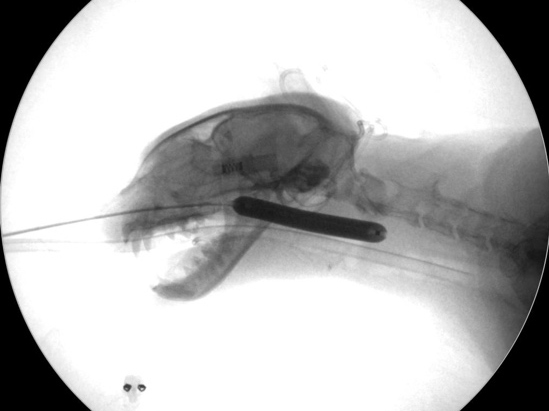

バルーン拡張術の様子

Cアームにて拡張部位の確認